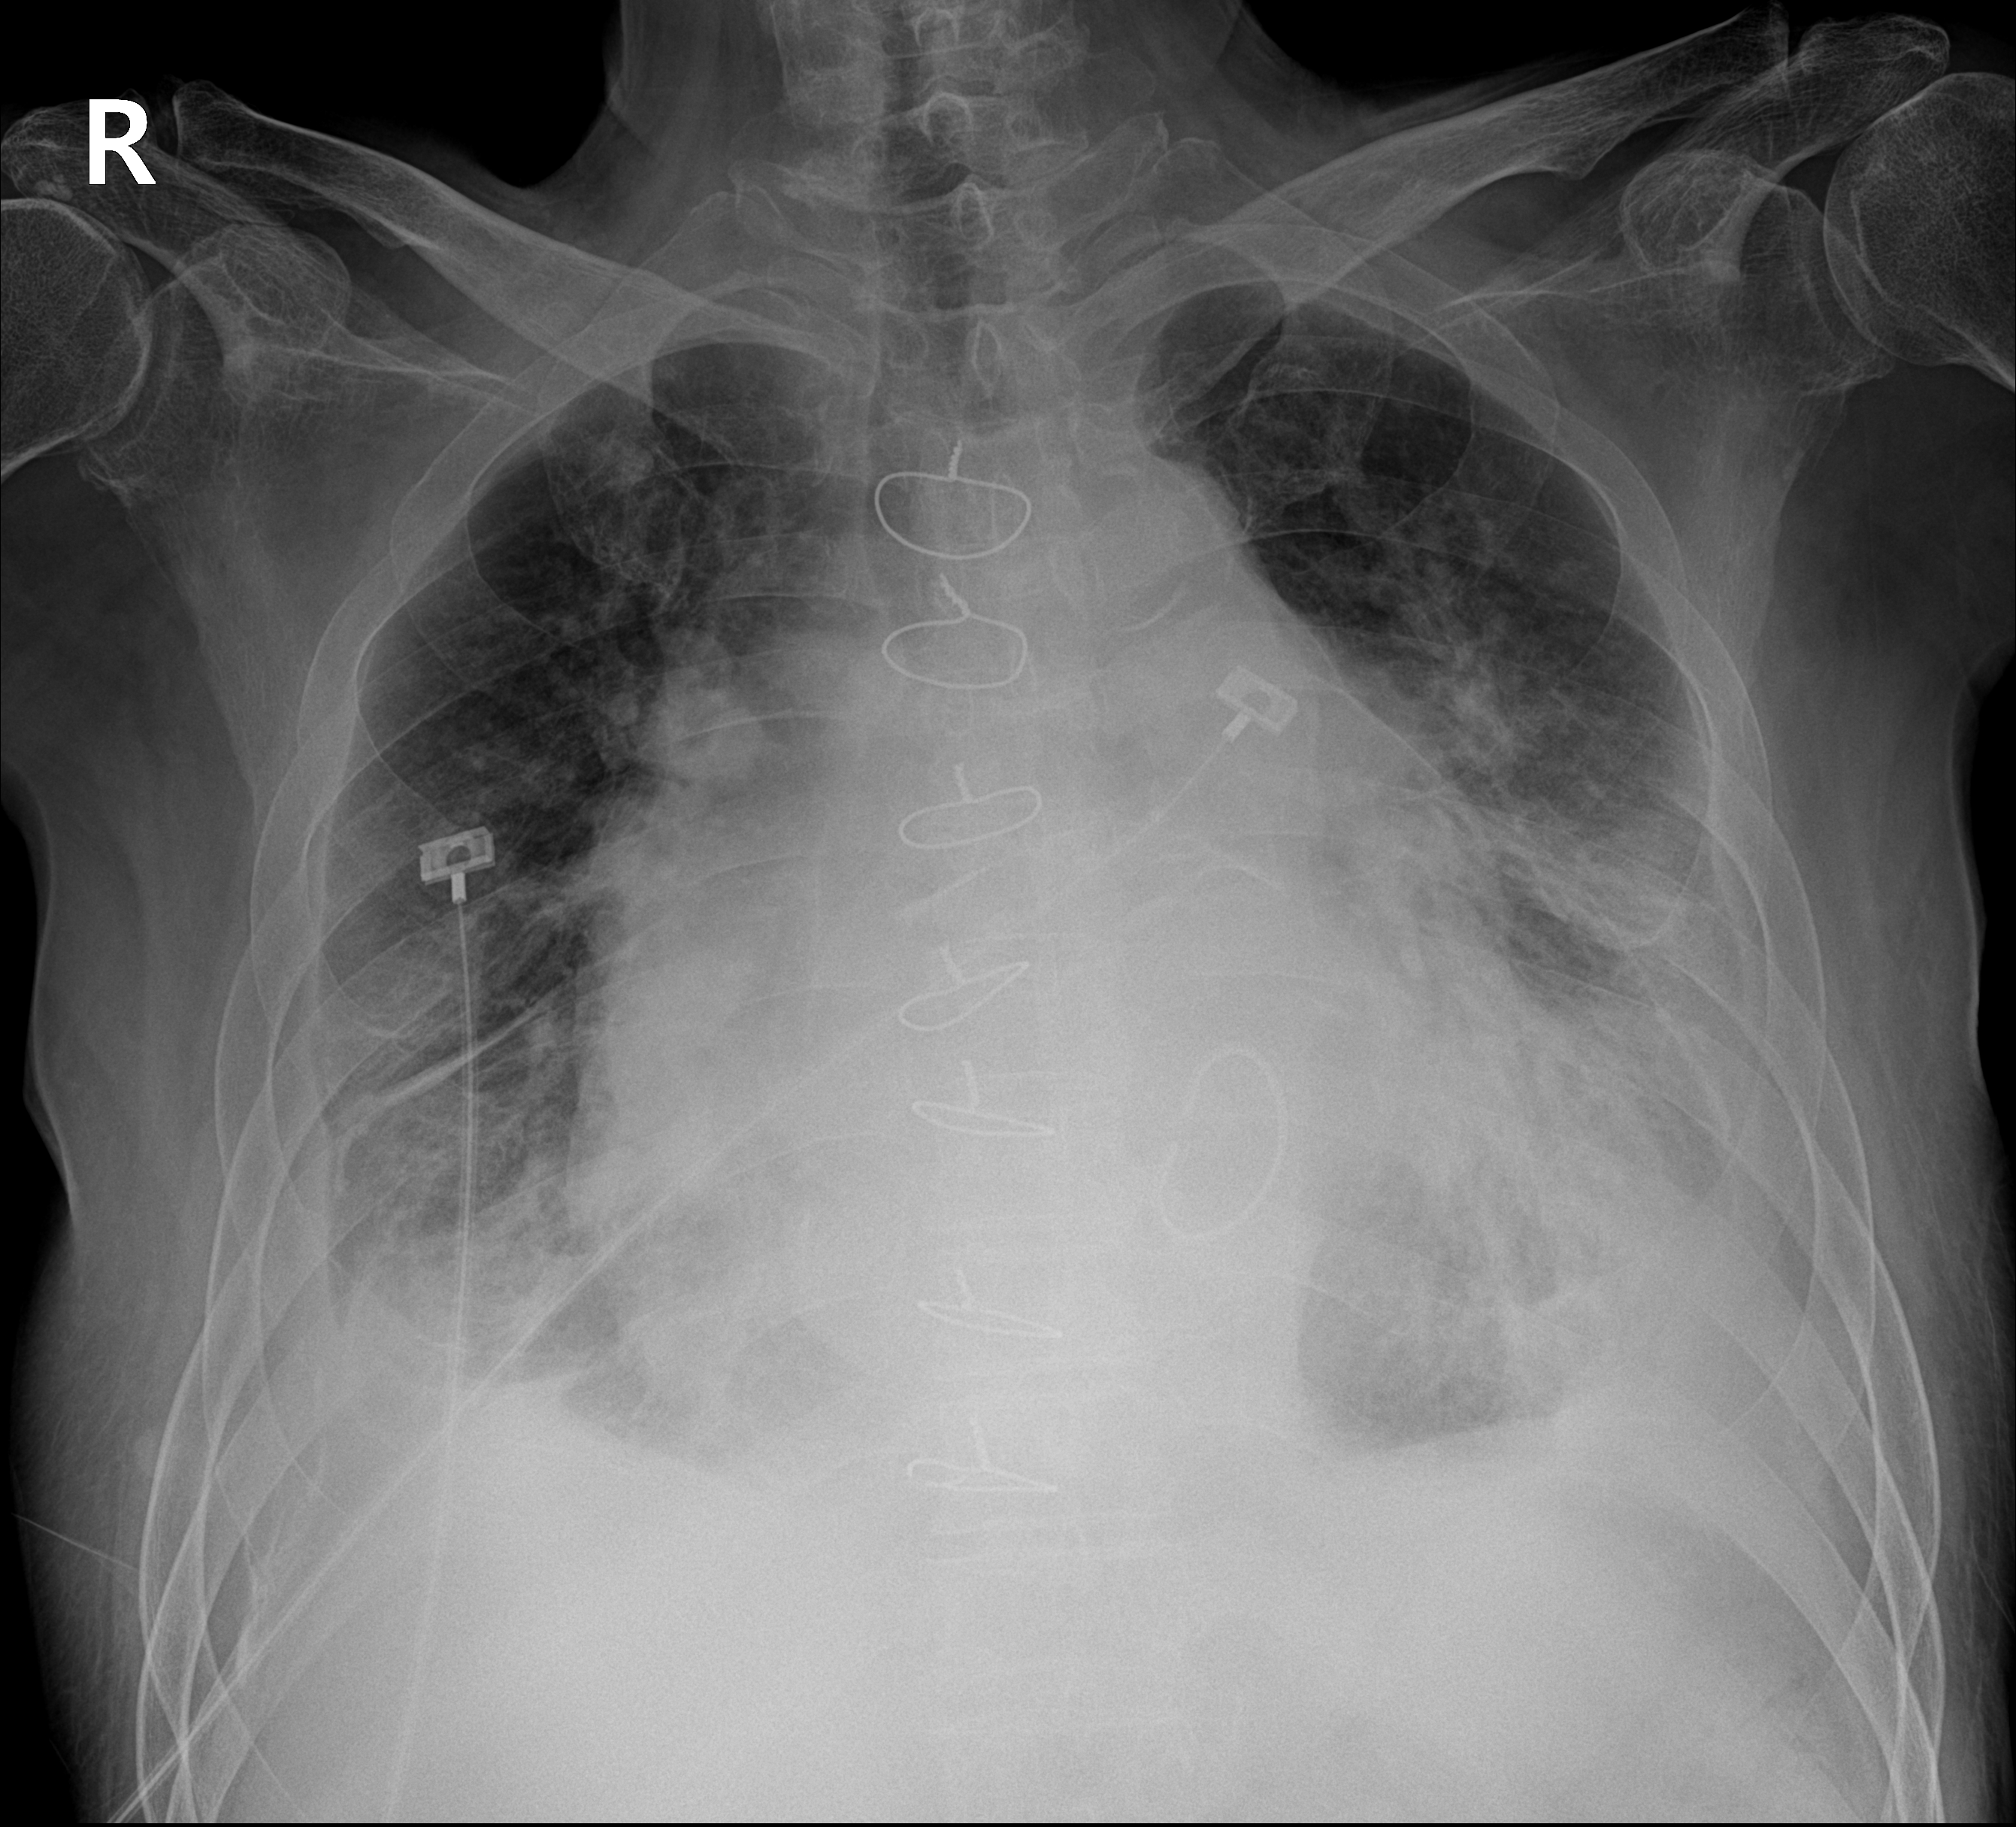

2) 폐질환 배제를 위한 가슴 X-ray, 폐기능검사 및 폐 CT

1) 갑상선기능검사를 포함한 정규 혈액검사, 폐기능 검사, 가슴 x-ray, 경흉부 및 경식도 초음파, 폐혈관 CT, ventilation/perfusion scan, HIV 항체검사